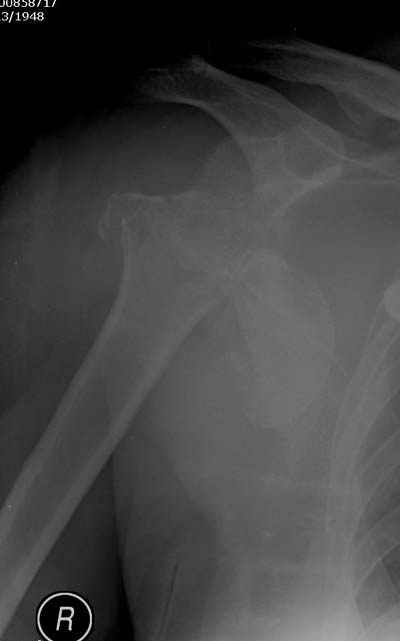

Здесь случай перелома-вывиха плеча, больному 56 лет, после "дважды" закрытой неудачной репозиции, опять же ургентно взяли в операционную, после полного общего обезболивания попытались сделать репозицию, и фиксацию провели спицами.

Больной находился в повязке, примерно напоминяющей косыночную, рекомендованы движения в локтевом суставе и маятниковые движения в плече, спицы удалены в три недели (были случаи миграции)

Больной амбулаторный, предупрежден на случай осложнения АВН головки.